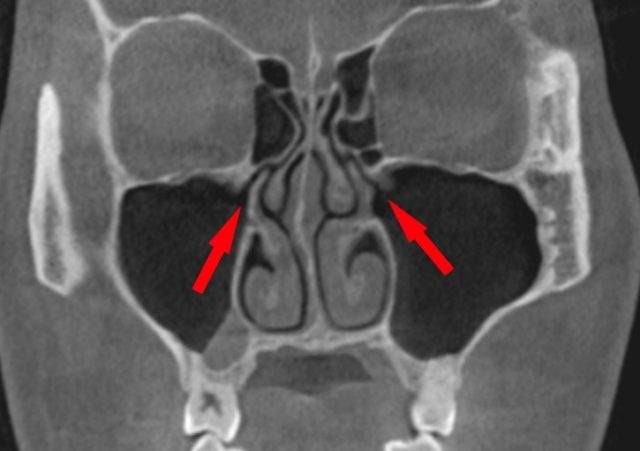

頬骨を押すと痛いのは、(赤矢印)

炎症がある上顎洞(赤丸)の

上顎洞の壁(前壁)を

押しているからです。

頬骨を押すと痛いとか、

頬骨を触ると痛くなります。

上図では、

上顎洞前壁の骨の厚みは、

0.9mmから1.2mmです。

炎症は、壁を通り越して、

表の皮膚まで痛くなります。

左右の頬骨が痛い

両方の頬骨が痛い時は、

鼻が原因の可能性が高くなります。

風邪、アレルギー性鼻炎など。

左右両側性に起ることが多いでしょう。

左右の頬骨が痛いときは、

歯が原因の可能性は低い

と思われます。

左右の歯が同時に、

上顎洞に炎症を起こす確率は低い

からです。